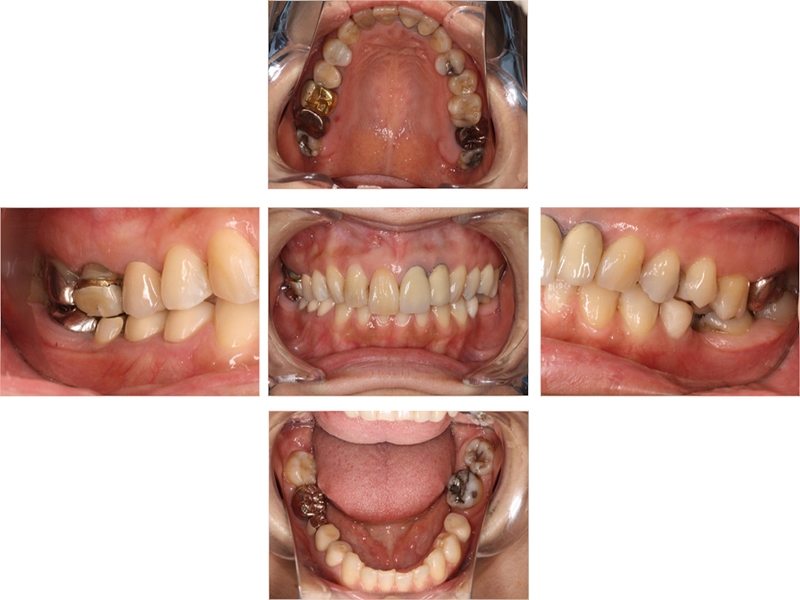

▼ ケース4.Upright症例

初診

治療中

before

after